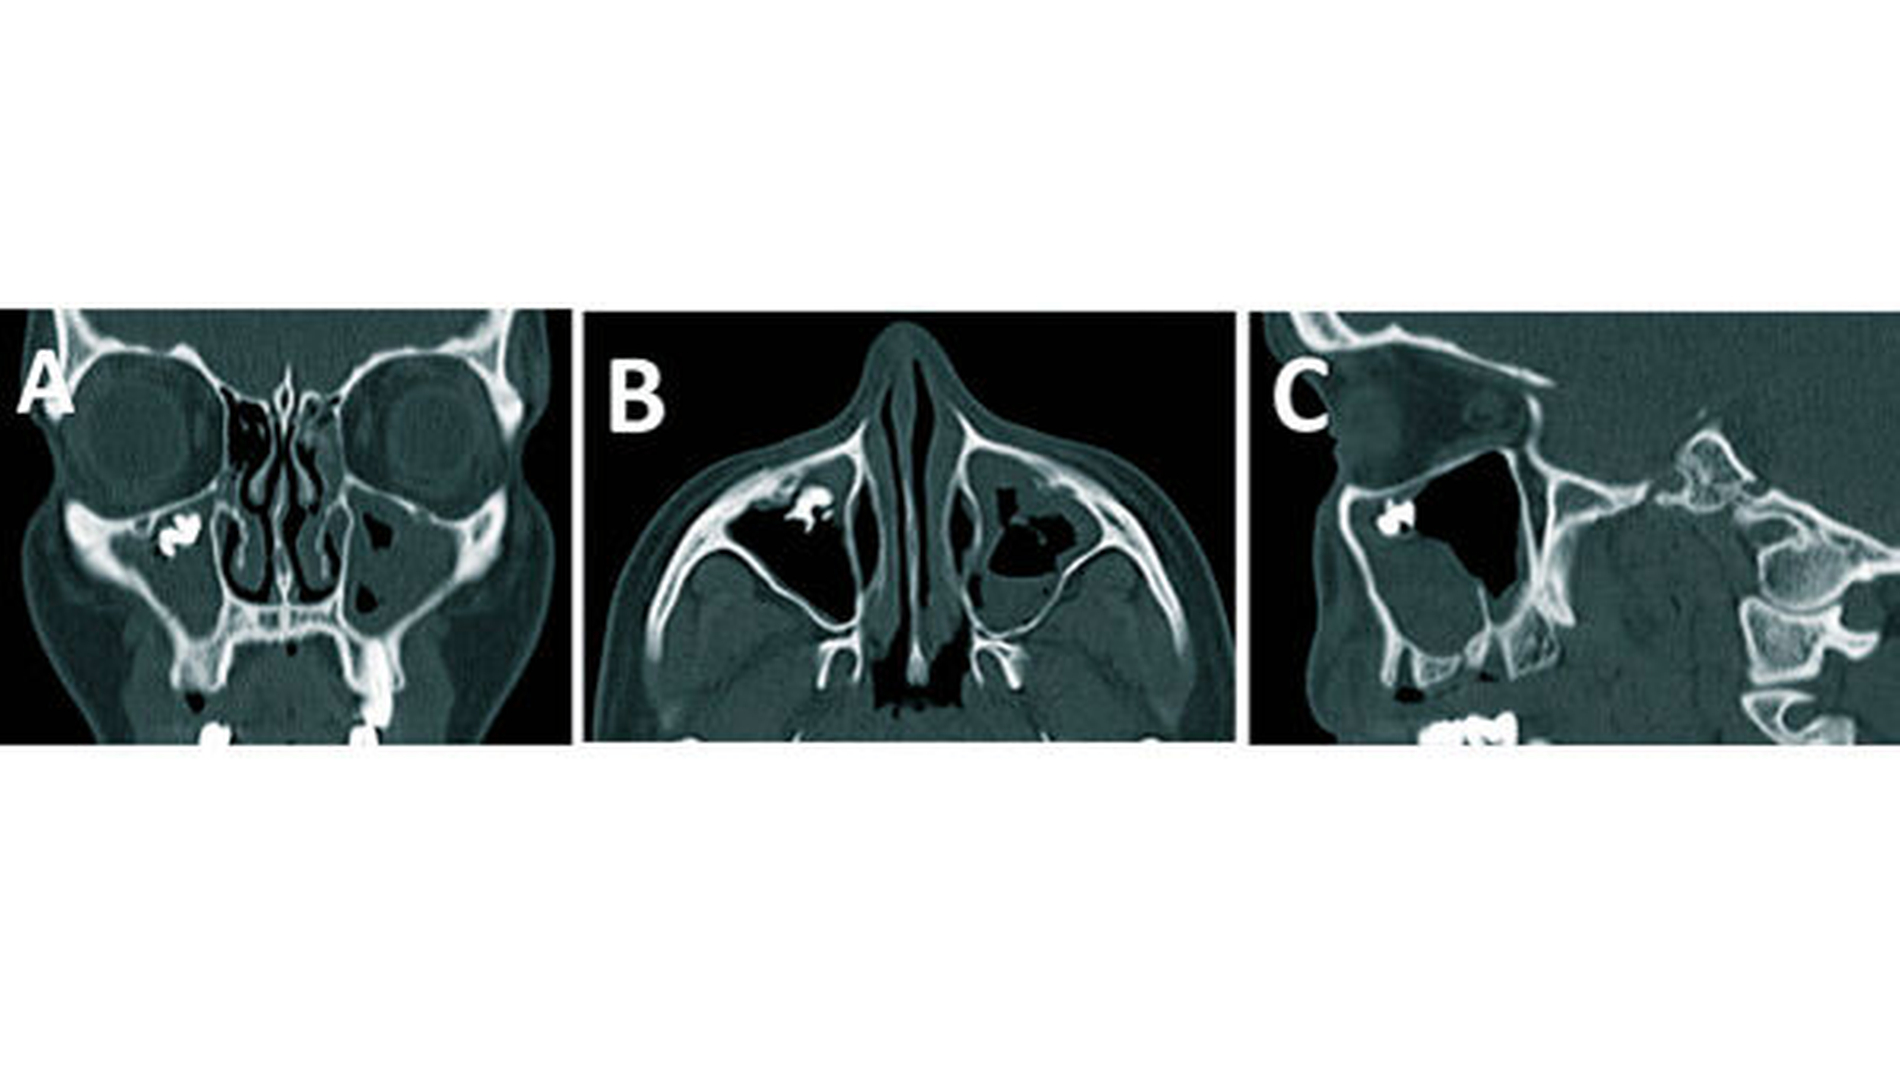

Das angefertigte Orthopantomogramm (OPT) stellte den aktuellen Zahnstatus mit dem Nebenbefund einer röntgendichten Verschattung im Sinne eines Fremdkörpers unterhalb des rechten Kieferhöhlendachs dar (Abbildung 1). Es folgte die Anfertigung eines NNH-CT zur genauen Lokalisierung des Fremdkörpers (Abbildung 2) für die anschließende OP-Planung.

In unserem Fall zeigte sich der röntgenopake Fremdkörper im OPT als Zufallsbefund. Zur genauen Lokalisation ist jedoch eine zwei- bis dreidimensionale radiologische Darstellung notwendig [Ferguson, 2014]. Bei der zweidimensionalen Darstellung bietet sich zum OPT ein Fernröntgenseitenbild und bei der dreidimensionalen ein DVT, NNH-CT sowie im Fall von nicht ferromagnetischen Fremdkörpern auch ein MRT an.